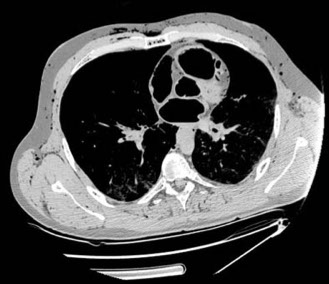

Air embolism from stab wound

Patients with stab wounds to the neck or penetrating chest trauma are at high risk of traumatic air embolism

Positive pressure ventilation of the affected lung will cause rapid death if the condition is not immediately recognized